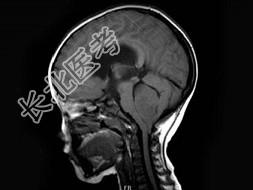

- 单项选择题女,3岁, 头痛4个月,MRI平扫及增强扫描, 最可能的诊断为 ( )

A、第四脑室脑膜瘤

B、第四脑室室管膜瘤

C、第四脑室乳头状瘤

D、第四脑室星形细胞瘤